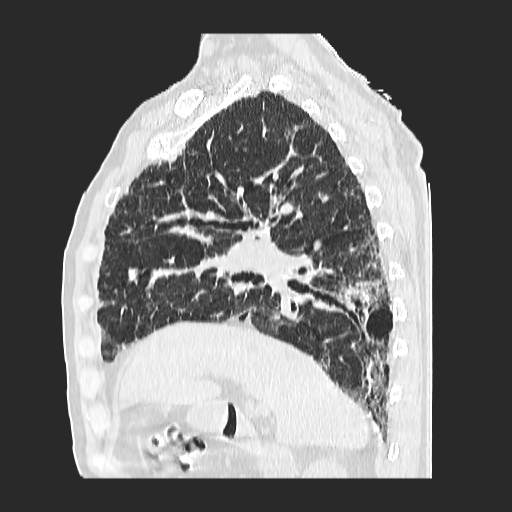

El parénquima pulmonar izquierdo muestra un infiltrado intersticial difuso que causa engrosamiento del septum axial, además del fenómeno de bronquiectasias quísticas se observan pequeñas bulas enfisematosas de localización subpleural que compromete ambas bases pulmonares.

Se observan imágenes de vidrio despulido en todo el lóbulo inferior izquierdo, el cual compromete los segmentos de la língula del segmento superior y medio

El parénquima pulmonar derecho muestra infiltrado intersticial en imagen de vidrio despulido con evidencia de lesiones subpleurales que representan bullas enfisematosas de diferentes tamaños.

Al utilizar un contraste Minip, se observan bronquiectasias cilíndricas en el extremo del lóbulo superior derecho, observándose un patrón de panal de abeja situada en la región apical del lóbulo superior izquierdo.

Bronquiectasias cilíndricas, bullas enfisematosas basales bilaterales